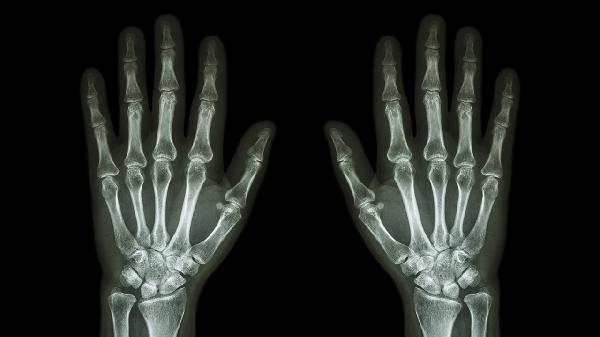

手法复位是月骨掌侧脱位的首选治疗方法,适用于单纯性脱位且无合并骨折的情况。医生会在局部麻醉下通过牵引和反向施力使月骨恢复原位。复位后需进行X线检查确认位置是否正确。手法复位成功的关键在于早期干预,脱位时间越长复位难度越大。复位过程中可能出现短暂疼痛,但通常可以耐受。

石膏固定是复位后的常规处理方式,需维持腕关节于轻度掌屈位固定4-6周。石膏范围通常从前臂中段至掌指关节,确保月骨稳定。固定期间需定期复查X线,观察月骨位置及血供情况。拆除石膏后应逐步进行腕关节功能锻炼,避免关节僵硬。患者需保持石膏干燥清洁,防止皮肤并发症。

手术治疗适用于手法复位失败、合并骨折或陈旧性脱位等情况。常用术式包括月骨切开复位内固定术、腕关节镜辅助复位术等。手术可精确恢复月骨解剖位置,同时处理合并损伤。术后仍需石膏固定4-6周,并配合康复训练恢复腕部功能。手术风险包括感染、神经损伤、关节僵硬等,需由经验丰富的医生操作。